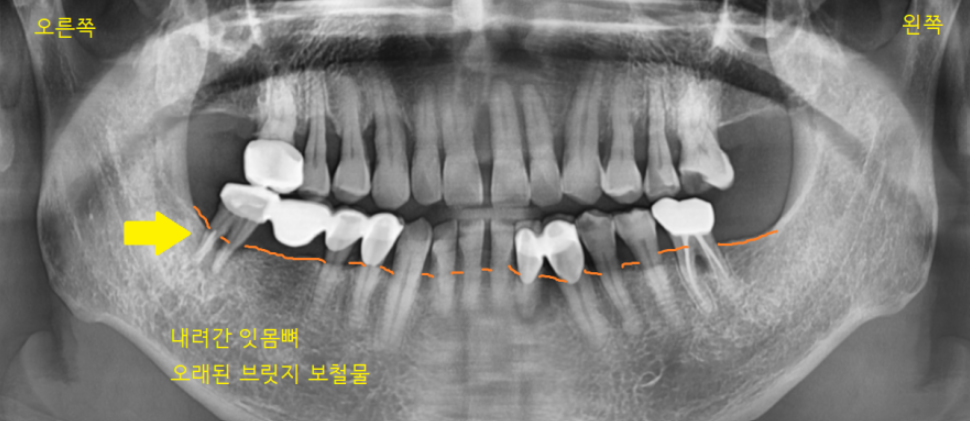

사진 속 화살표 치아를 주목해 주세요.

브릿지 치료가 되어있네요.

정상적인 잇몸뼈는 치아머리 부위까지

채워져 있어야 합니다.

잇몸뼈가 많이 내려가서

치아를 붙잡고 있는 게 없다 보니

흔들흔들했는데요.

4개가 연결되어 있지만

검사 후 잇몸뼈가 남아있는 부분은

그대로 쓰시기로 했습니다.